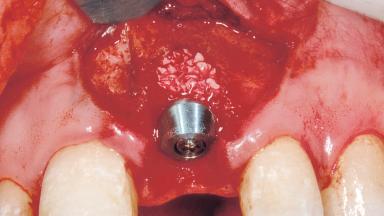

Immediate Placement of an Implant in a Maxillary Left Central Incisor Site

A 33-year-old female patient presented with an upper left central incisor that required extraction after a failed endodontic therapy. The tooth had been traumatized when the patient was a teenager and had undergone several endodontic treatments, including two apicectomy procedures. The patient was in good health and did not smoke. Clinical examination showed that the patient had a high lip line. In full smile, the gingival margins of the upper teeth were visible to the first molars. The gingival margins of central incisors 11 and 21 were only just showing. Examination of tooth 21 confirmed that the tooth was mobile and had hypererupted by 1 mm.

Bone Augmentation Horizontal|Simultaneous

Augmentation Materials Xenogenous|Membrane

Soft Tissue Grafting Simultaneous

Placement Protocol Immediate implant placement

Socket Integrity Damage to one or more bone walls

Bone Volume Damage to one or more socket walls